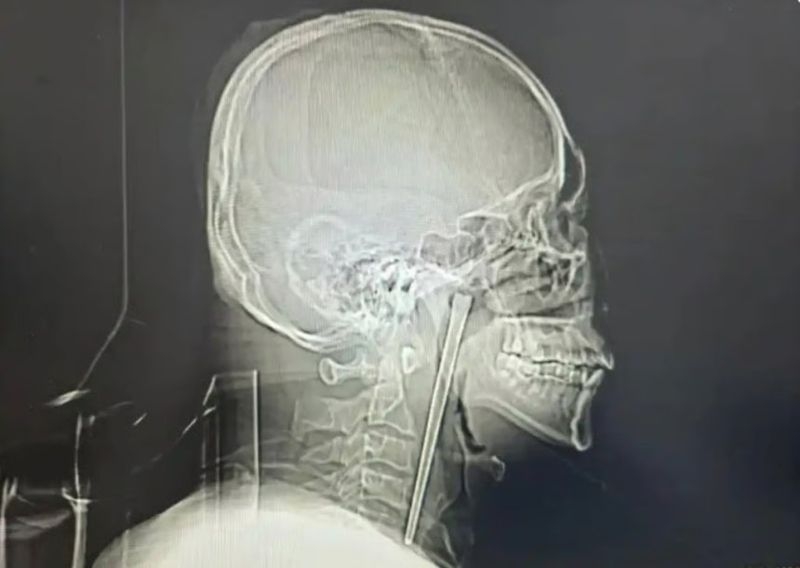

19일(현지시간) 사사우스차이나모닝포스트(SCMP)는 이달 초 중국 랴오닝성 북동부 다롄 시립중앙병원에서 8년 전 삼킨 젓가락을 제거하는 수술을 받은 왕씨에 대해 보도했다.

정밀 검사 결과 왕씨가 삼킨 금속 젓가락은 입천장의 뒤에 위치한 목 안쪽 연구개 부위에 박혀 있었던 것으로 확인됐다.

의료진은 “다행히 주변 점막이 손상되지 않았고 성대 기능 역시 정상적으로 유지되고 있었다”고 설명했다.

그러나 왕씨가 여전히 목 절개 수술을 거부, 의료진은 절개를 최소화한 최소 침습 수술을 진행했다. 다행히 구강을 통해 소량의 출혈만으로 젓가락을 제거하는 데 성공했다. 빠르게 회복한 왕씨는 며칠 후 퇴원했다.